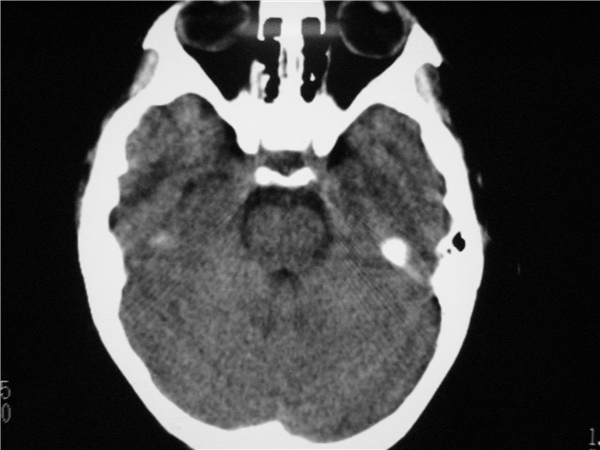

以下是引用随光逐影在2009-8-1 14:17:00的发言:[br]透明隔囊肿与vergae腔并存。

以下是引用zjzjr在2009-8-1 14:51:00的发言:[br]五、六脑室形成。